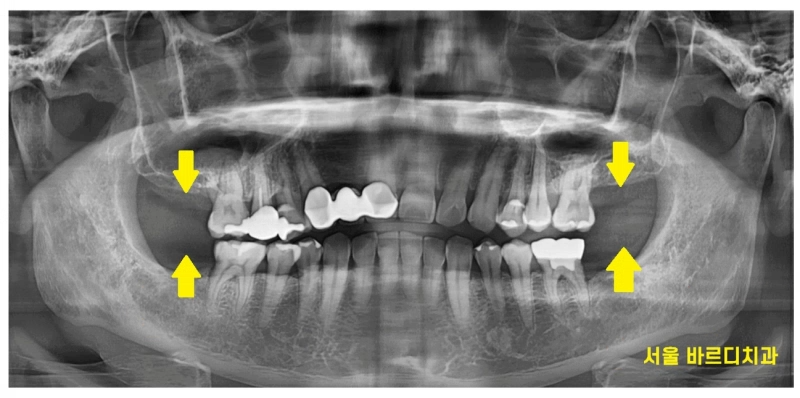

명일동 치과를 처음 방문하셨을 때 사진입니다.

보시는 것처럼

위, 아래

오른쪽, 왼쪽

사이좋게 양쪽 맨 끝 어금니를

상실하신 채 내원하셨어요.